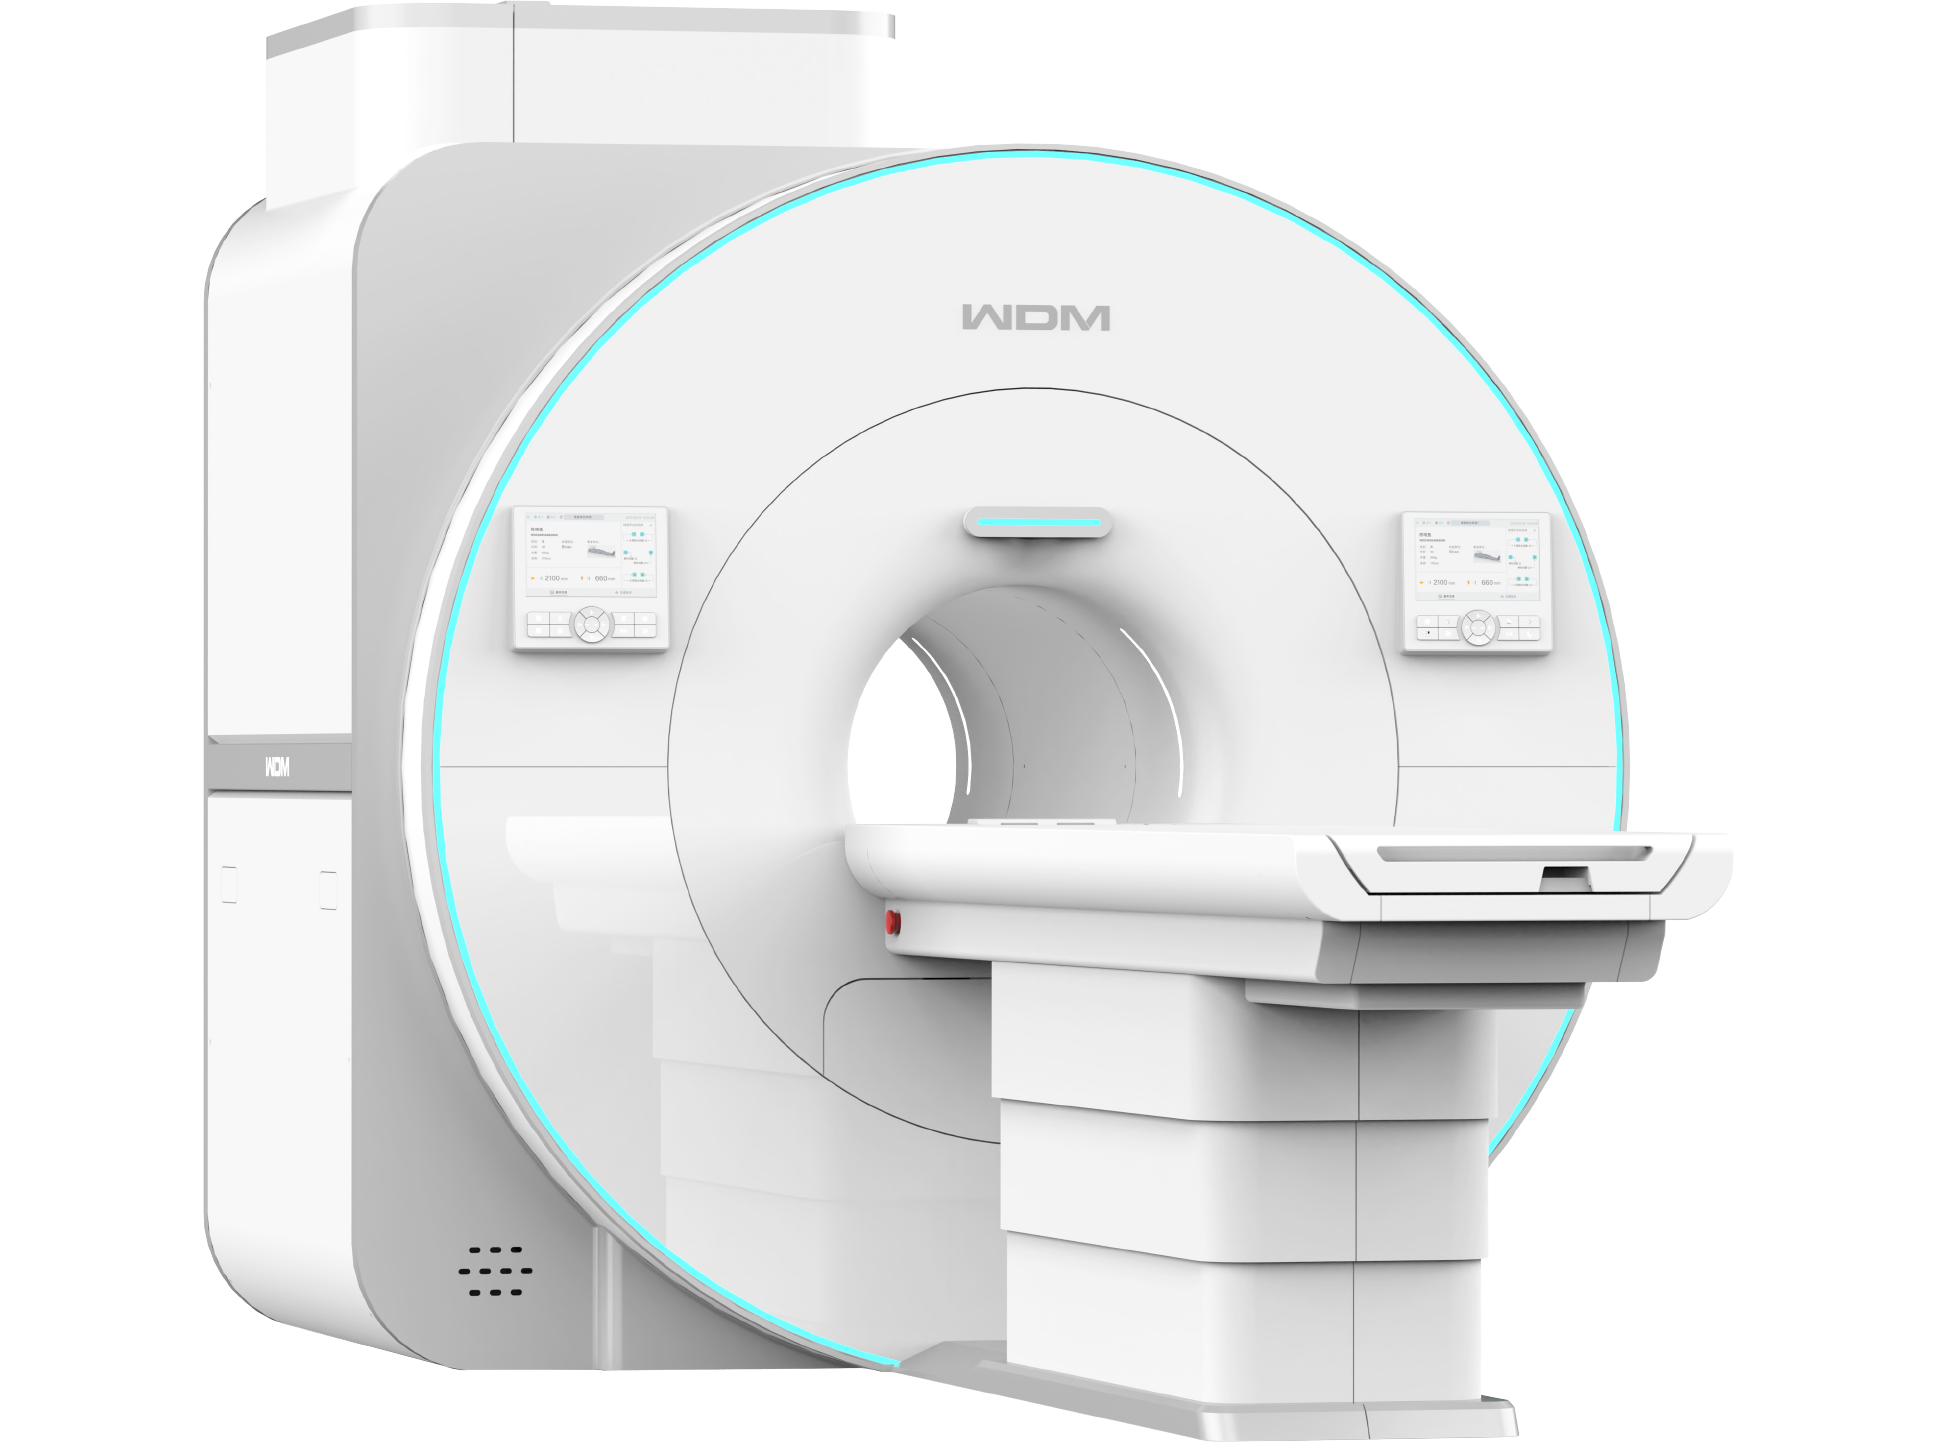

32通道高性能,媲美3T

十大智能技术,打造磁共振优质性能

十大智能技术,打造磁共振优质性能

真32通道系统

多通道线圈与多通道谱仪一一独立对应,配合快速并行采集技术改善成像速度。

智能全数字化

光纤传输

采集系统,梯度系统,射频系统全部数字化,光纤传输,有效减少信号衰减,避免干扰,改善信噪比。